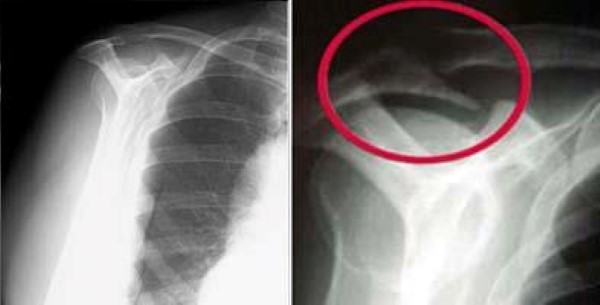

X-rays. Because X-rays do not show the soft tissues of your shoulder like the rotator cuff, plain X-rays of a shoulder with rotator cuff pain are usually normal or may show a small bone spur. A special X-ray view, called an outlet view, sometimes will show a small bone spur on the front edge of the acromion.

shoulder x-ray outlet views of normal and bone spur

(Left) Normal outlet view X-ray. (Right) Abnormal outlet view showing a large bone spur causing impingement on the rotator cuff.

Images courtesy of Stuart J. Fischer, MD, FAAOS